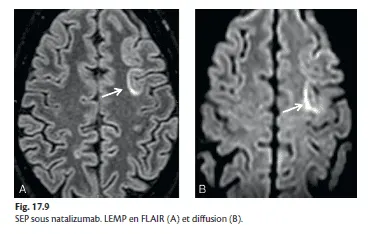

en rapport avec l'immunosuppression due à certains traitements, en particulier une LEMP compliquant un traitement par natalizumab (Tysabri®) ou immunosuppresseur, ou un IRIS à l'arrêt de ce traitement (fig. 17.9).

Figure 17.9